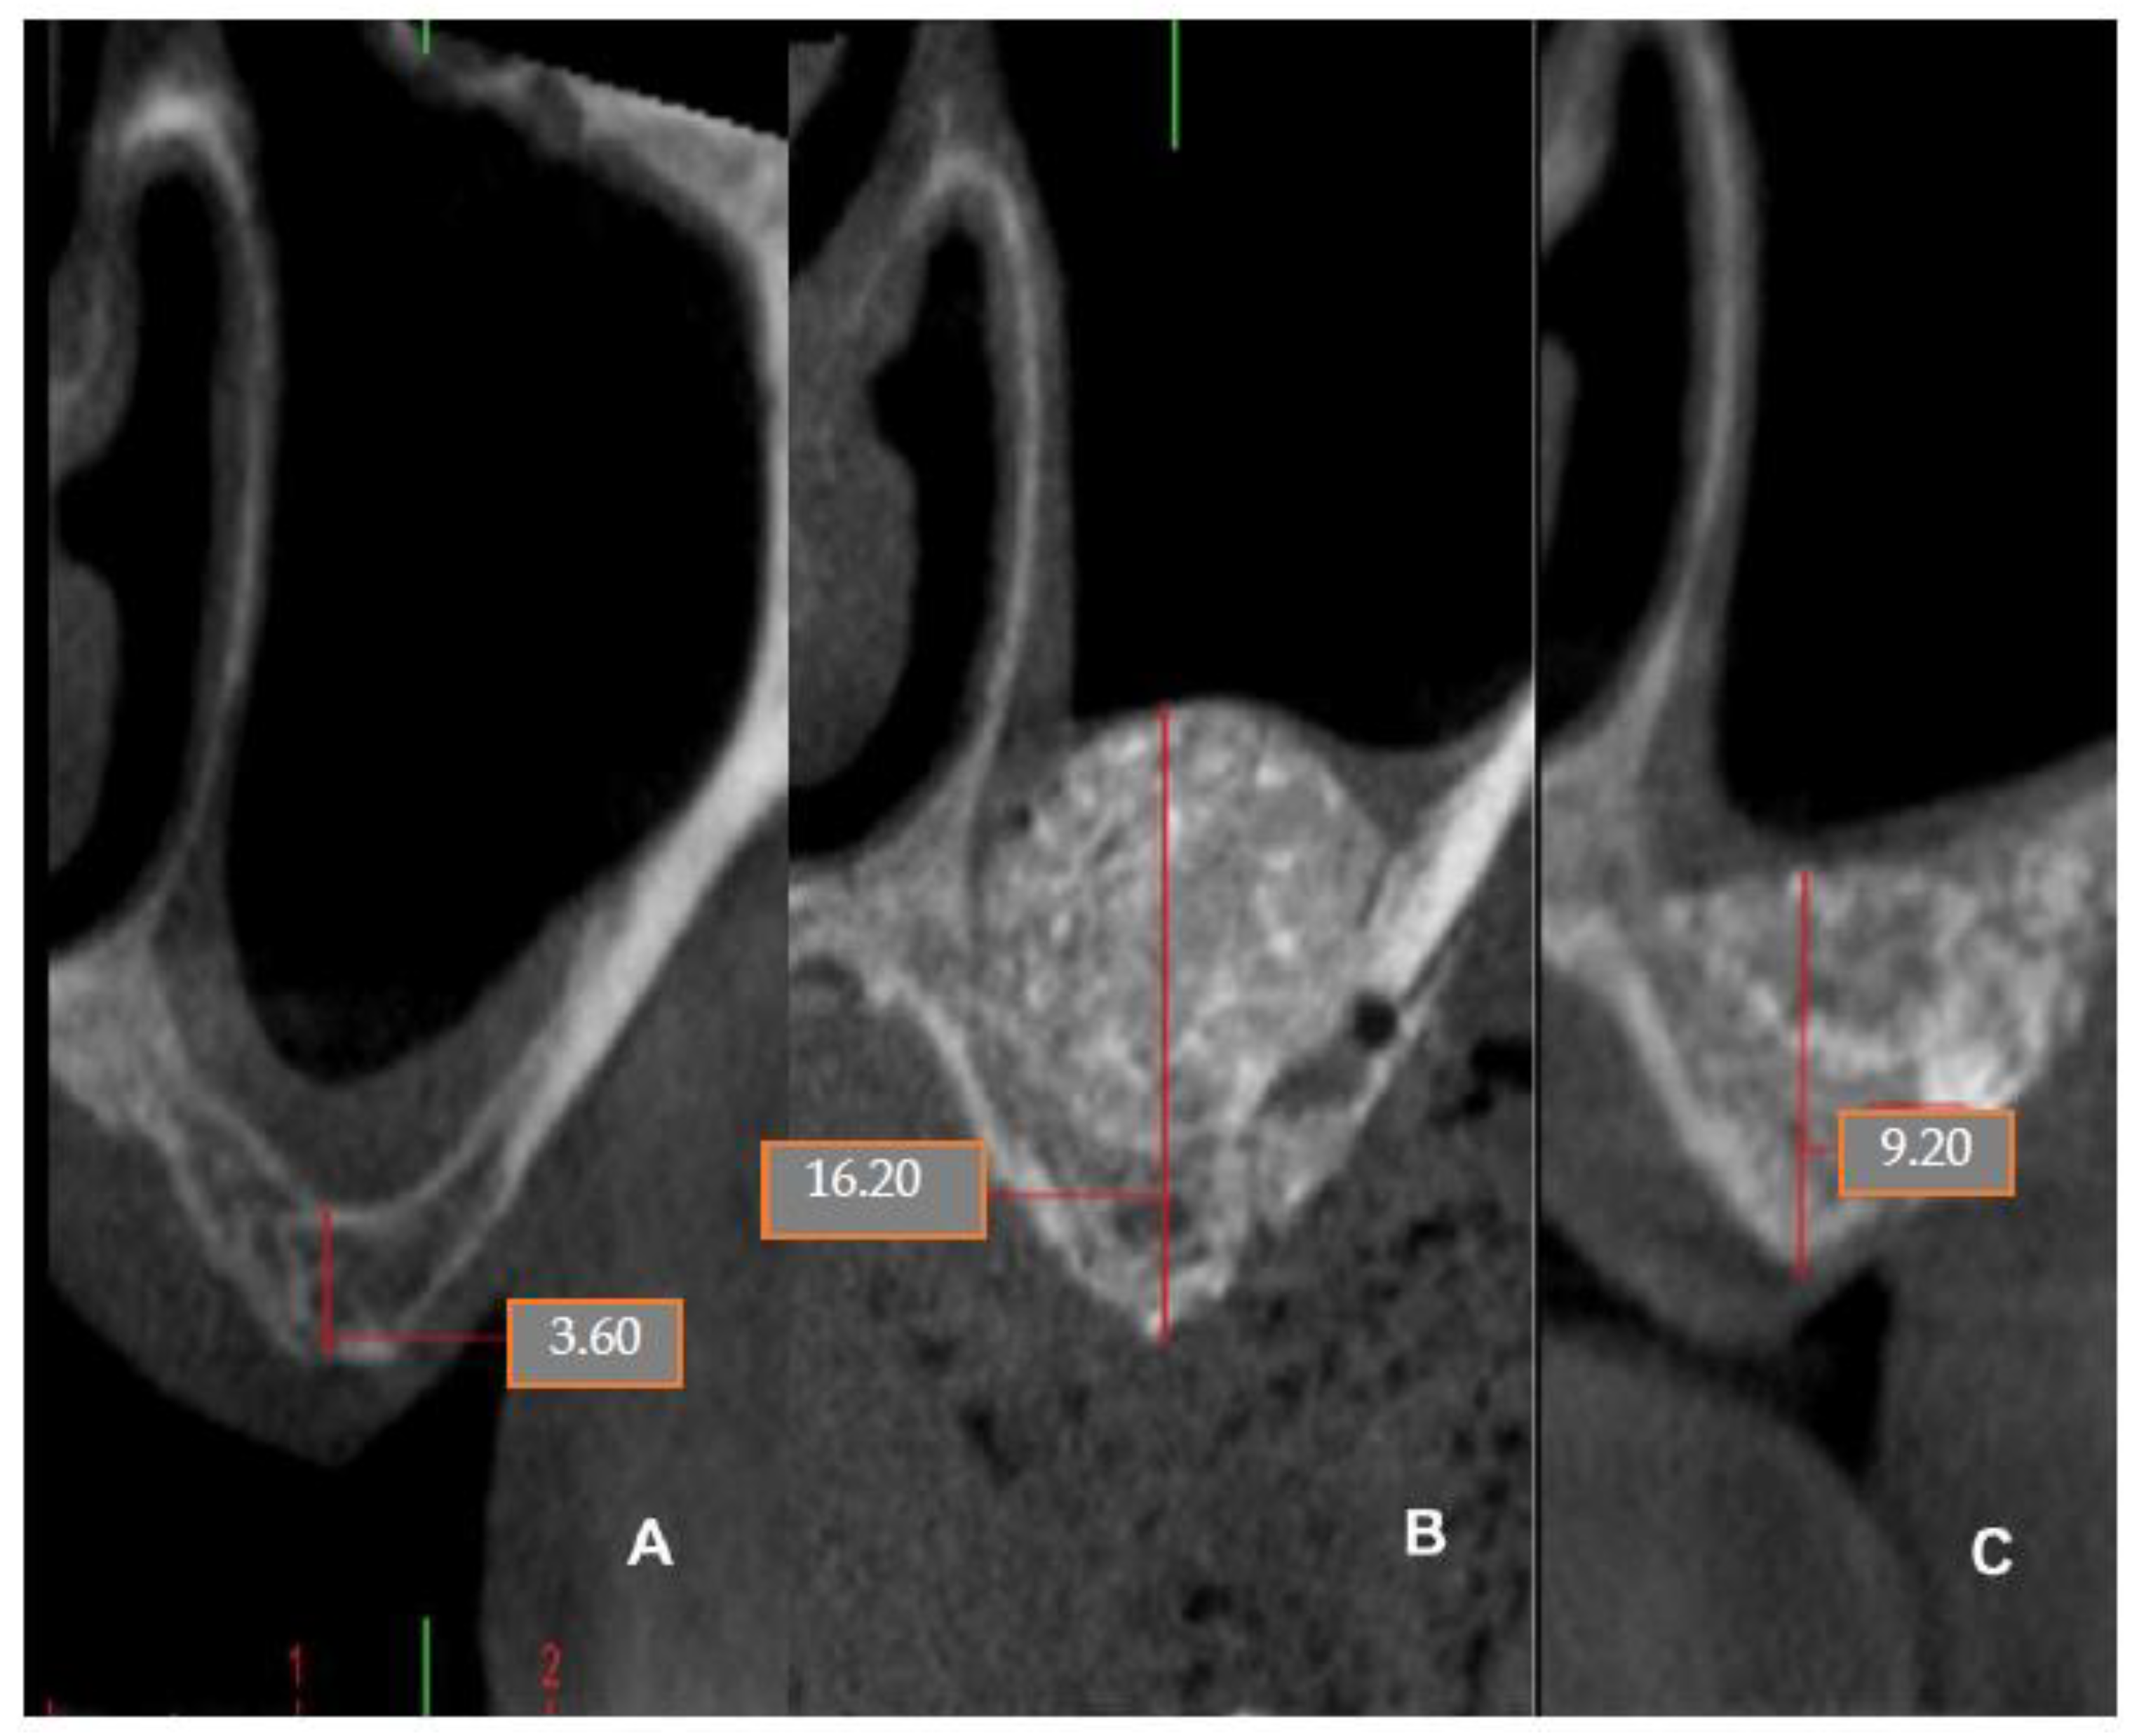

4.5. Patient No.5

4.6. Patient No.6